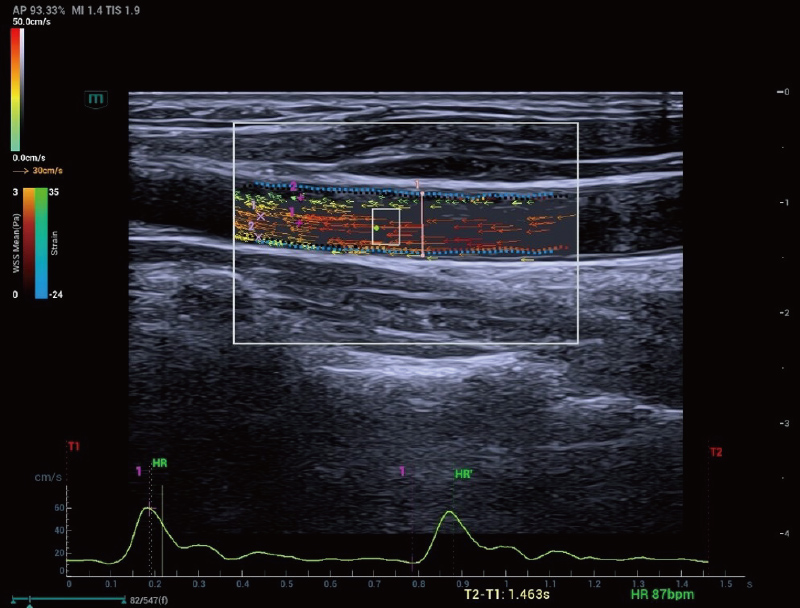

De Resona A20 introduceert een nieuwe generatie vasculaire, kwantitatieve analysetools met op RF-gegevens gebaseerde analyse van vasculaire pulsgolfsnelheid en wandschuifspanning. Deze ontwikkelingen helpen bij de beoordeling van arteri?le vasculaire sclerose.

V Flow en analyse van wandschuifspanning

Arteria carotis | Holo-PWV